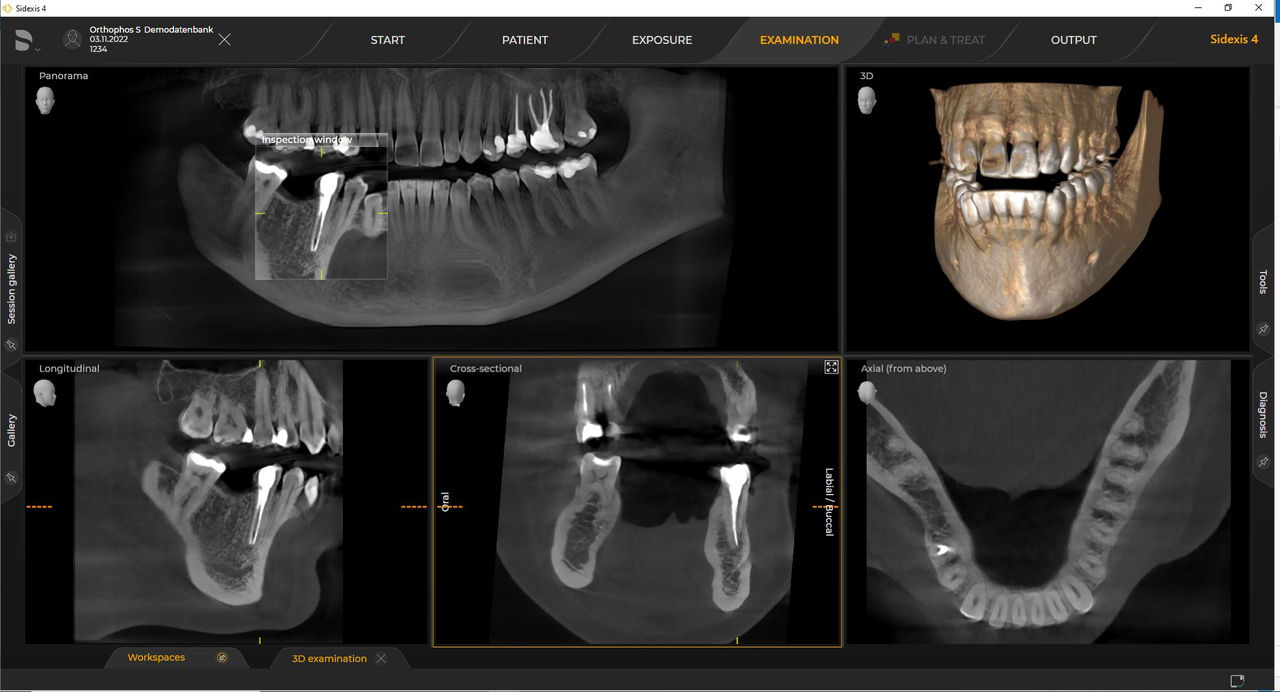

Das hochwertige 2D/3D-Röntgengerät mit umfassendem Leistungsspektrum für jede Praxis. Ob als reines 2D-Gerät oder mit integriertem 3D-Modul – Orthophos S ist ein zuverlässiger Partner und optimiert für alltägliche Aufgaben. Gestochen scharfe Aufnahmen dank CsI-Plus-Sensor und Autofokus. Die automatische Patientenpositionierung zusammen mit dem patentierten Okklusalaufbiss ermöglicht eine einfache und zeitsparende Patientenpositionierung. Für den Einsatz in der Kieferorthopädie ist der Orthophos S auch mit einem optionalen Ceph-Arm erhältlich. Und da Zukunftssicherheit für Dentsply Sirona wichtig ist, kann der Fernröntgenausleger jederzeit nachgerüstet werden.

Mit dem Intelligent Low Dose-Modus erhalten Sie 3D-Röntgenbilder im Dosisbereich einer 2D-Röntgenaufnahme. Im HD-Modus werden während eines einzelnen Umlaufs bis zu 1.400 Einzelbilder aufgenommen und zu einem 3D-Volumen mit bis zu 80 μm zusammengeführt. Der Vorteil für Sie: rauschärmere Aufnahmen in hoher Auflösung.

Dentsply Sirona Röntgengeräte arbeiten exklusiv mit Sidexis 4. Aber die Datenmigration von Sidexis XG zu Sidexis 4 ist sehr einfach. Wir empfehlen den Wechsel zu Sidexis 4, um die vollen Vorteile des digitalen Prozesses mit den neuesten Werkzeugen zu erleben.